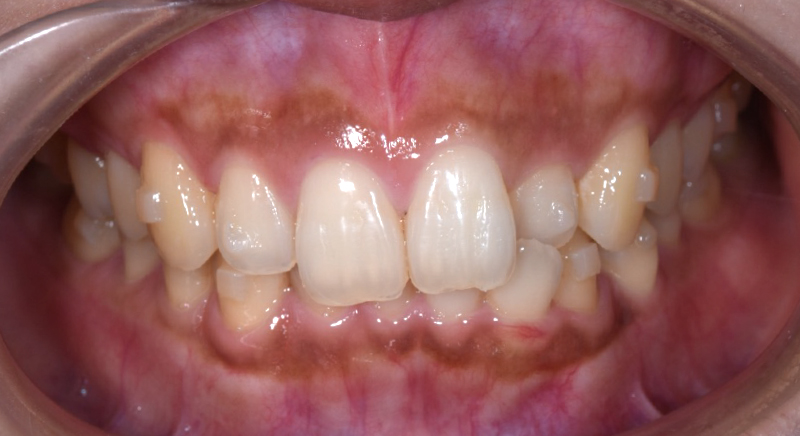

| 主訴 | 歯並びを治したい |

| 治療期間 | 5か月 |

| 治療費 | 部分マウスピース矯正(モニターキャンペーン)と ホワイトニングセット 422,596円(税込) |

| 治療内容 | 目立ちにくいマウスピース矯正 (非抜歯矯正) 歯と歯の間に隙間をつくることにより、歯列弓を広げながら治療を行いました。 また矯正用マウスピースをトレー代わりにし、ジェルを入れてホームホワイトニングを同時に行っております。 |

| 治療のリスク | ・後戻りする可能性があるのでリテーナーを最低でも矯正期間以上はつける必要があります。 ・ホワイトニング後、一時的に痛みが出る場合があります。 |